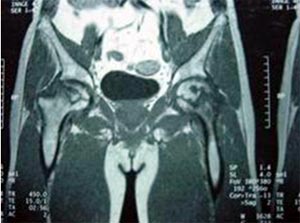

MRI显示股骨头坏死

患者35岁,双侧股骨头坏死。将患者的骨髓细胞与具有支撑力的植骨材料复合植入骨修复区。术后3年患者髋关节功能良好,无塌陷,无疼痛。